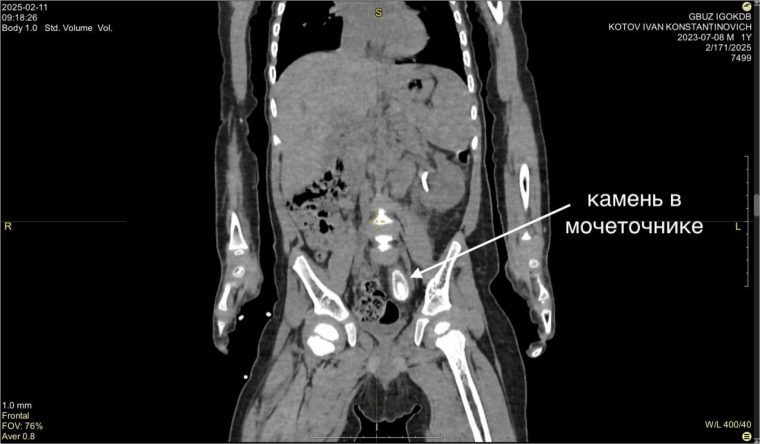

Первые признаки заболевания жительница Усть-Кута обнаружила у сына Вани еще в декабре прошлого года. На обследовании в Иркутске поставили диагноз — большой камень в нижней трети левого мочеточника размером около 3 на 1,5 см и вызванный им блок почки.

Размер камня удивил медиков — это нетипично для таких маленьких пациентов.

— Попытка внутрипросветного лечения была безуспешна — устье мочеточника не пропускало даже самую маленькую оптическую систему цистоскопа. После месяца непростого лечения с использованием нескольких антибиотиков была выполнена операция с применением нашего излюбленного подхода без разрезов — лапароскопии, — рассказывает Юрий Козлов.

Операция прошла успешно, и сегодня Ваня чувствует себя прекрасно.